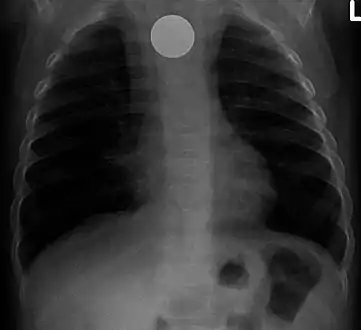

A coin seen on AP CXR in the esophagus

A coin seen on lateral CXR in the esophagus

AP X ray showing a 9mm battery in the intestines

Lateral X ray showing a 9mm battery in the intestines

Multiple button batteries in the stomach